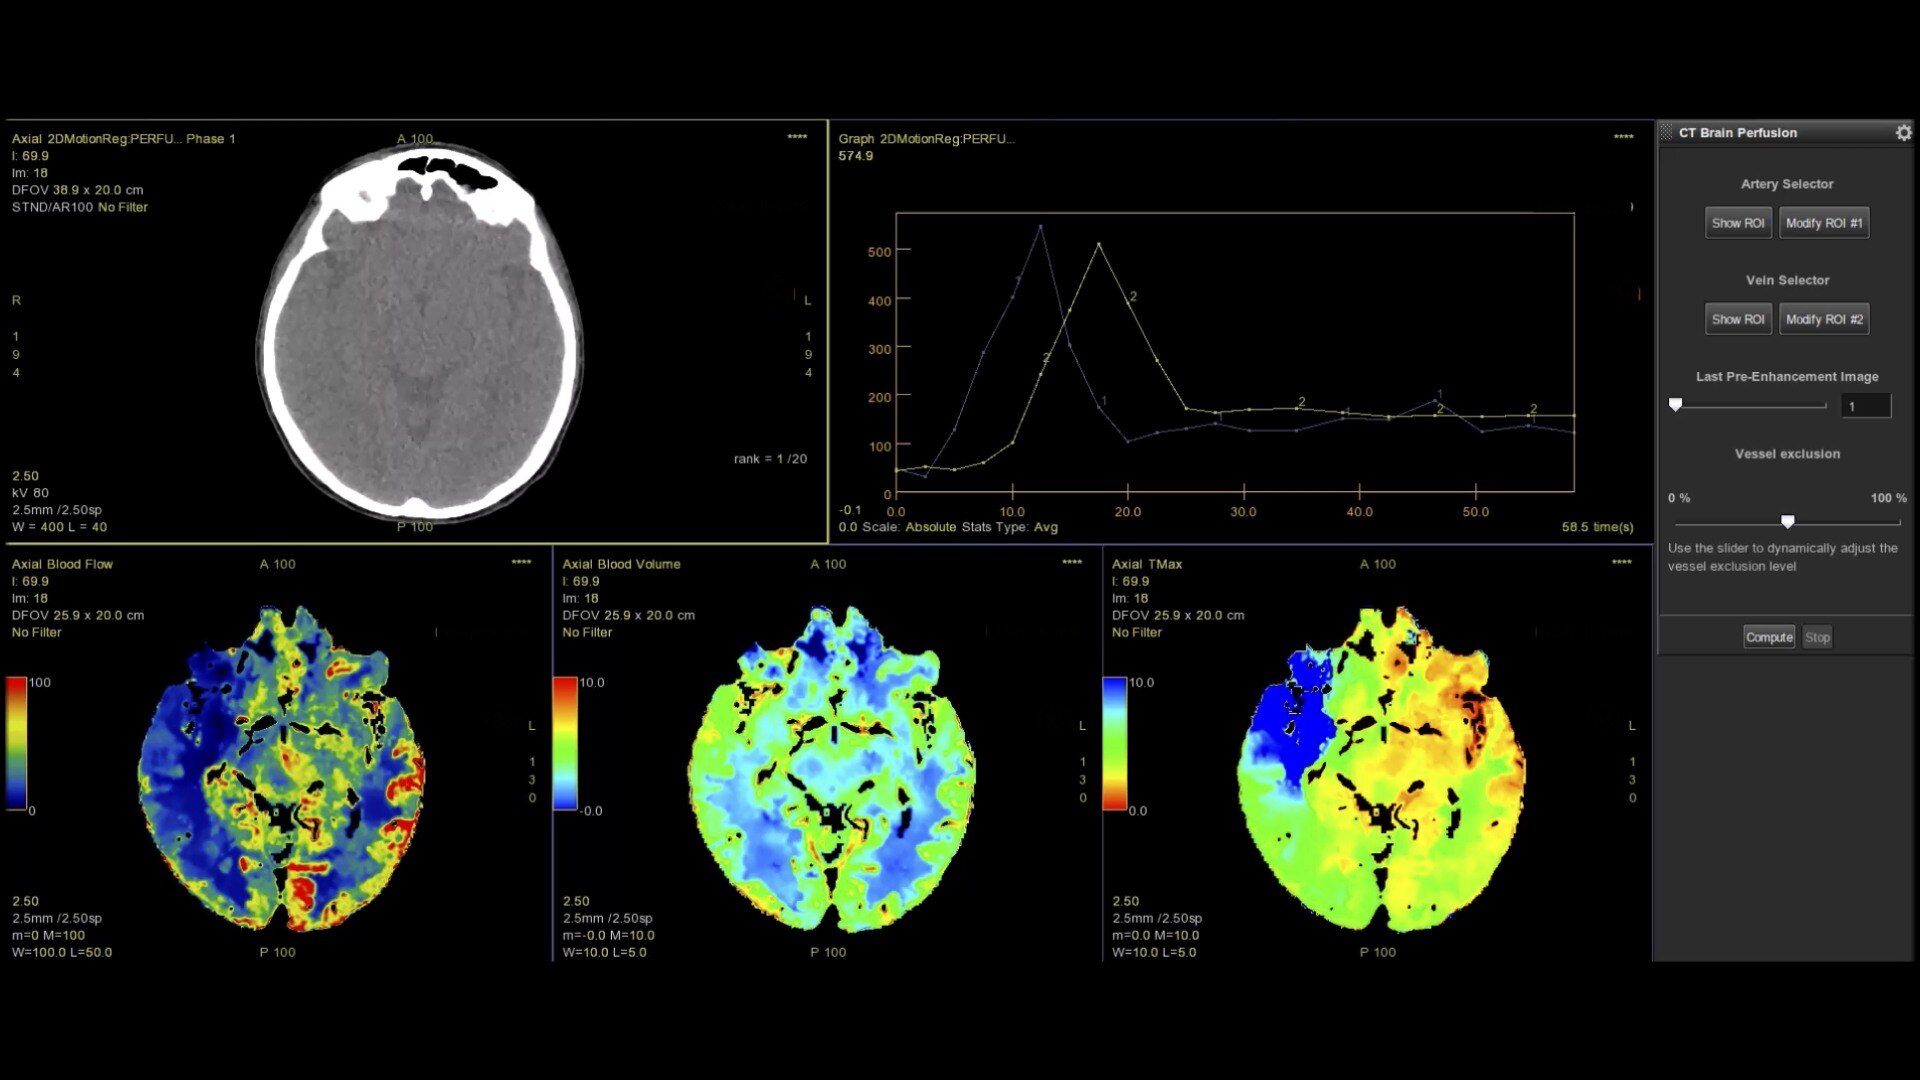

CT Perfusion 4D

Fast, easy-to-use automated software for analyzing CT Perfusion images related to stroke, tumor angiogenesis and dynamic myocardial perfusion.

Brain stroke protocol

• Image Registration to minimize the effects of patient movement

• Bone Removal to remove the cranium automatically from the dataset

• Deep Learning brain ventricle segmentation to prevent ventricular matter inclusion in quantitative results and improve visual inspection of the maps

• Automated selection of arterial input and venous output. Both can be easily adjusted if needed.

• Automated generation of all functional maps: Blood Flow, Blood Volume, Mean Transit Time, and Transit Time to IRF Peak (Tmax)

• Automatically define the symmetry plane to be used for mirroring ROIs and relative thresholds

• Tissue Classification enables the visualization of regions that are segmented from absolute or relative values, customizable thresholds and user selectable input maps

• Mismatch volume and ratio are calculated from the modified perfusion volume and low perfusion volume ROIs

CTPerfusionfeatureheroimage1